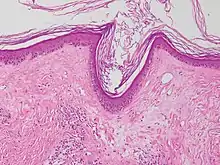

| Lichen planus | Irregular epidermal hyperplasia with a jagged “sawtooth” appearance, compact hyperkeratosis or orthokeratosis, foci of wedge-shaped hypergranulosis, basilar vacuolar degeneration, slight spongiosis in the spinous layer, and squamatization. The dermal papillae between the elongated rete ridges are frequently dome shaped. Necrotic keratinocytes can be observed in the basal layer of the epidermis and at the dermal-epidermal junction. Eosinophilic remnants of anucleate apoptotic basal cells may also be found in the dermis and are referred to as “colloid or civatte bodies”. Whickham striae are usually seen in the areas of hypergranulosis. Vacuolar degeneration at the basal layer may be noted leading to focal subepidermal clefts (Max Joseph spaces). Squamatization occurs as a result of maturation and flattening of cells in the basal layer. It happens in areas of marked hypergranulosis with prominence of the sawtooth pattern of rete ridges. Wedge-shaped hypergranulosis can occur in the eccrine ducts (acrosyringia) or hair follicles (acrotrichia). In the hypertrophic subtype, the associated hyperkeratosis, parakeratosis, hypergranulosis, papillomatosis, acanthosis, and hyperplasia markedly increased with thicker collagen bundles forming in the dermis. Moreover, the rete ridges are more elongated and rounded as opposed to the typical sawtooth pattern. In atrophic LP, loss of the rete ridges and dermal fibrosis is prominent. In vesiculobullous LP, the disease progression is quicker. Hence, some of the distinctive features such as hyperkeratosis, hypergranulosis, or dense lymphocytic dermal-epidermal infiltrate may not be present. LP lesion may resolve with residual hyperpigmentation caused by a persistent increase in the number of melanophages in the papillary dermis.[9] | ![]() | ![]() |